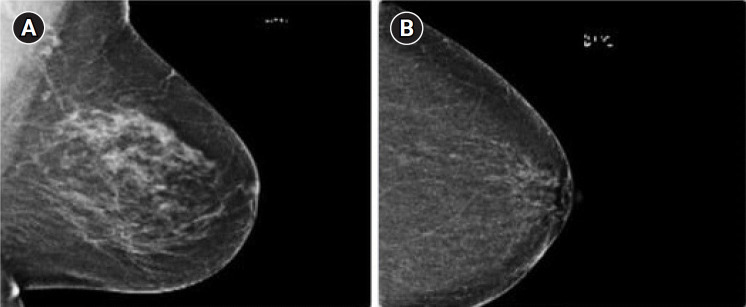

BCED-Net: Breast Cancer Ensemble Diagnosis Network using transfer learning and the XGBoost classifier with mammography images.

Background: Breast cancer poses a significant global health challenge, characterized by complex origins and the potential for life-threatening metastasis. The critical need for early and accurate detection is underscored by the 685,000 lives claimed by the disease worldwide in 2020. Deep learning has made strides in advancing the prompt diagnosis of breast cancer. However, obstacles persist, such as dealing with high-dimensional data and the risk of overfitting, necessitating fresh approaches to improve accuracy and real-world applicability.

Methods: In response to these challenges, we propose BCED-Net, which stands for Breast Cancer Ensemble Diagnosis Network. This innovative framework leverages transfer learning and the extreme gradient boosting (XGBoost) classifier on the Breast Cancer RSNA dataset. Our methodology involved feature extraction using pre-trained models-namely, Resnet50, EfficientnetB3, VGG19, Densenet121, and ConvNeXtTiny-followed by the concatenation of the extracted features. Our most promising configuration combined features extracted from deep convolutional neural networks-namely Resnet50, EfficientnetB3, and ConvNeXtTiny-that were classified using the XGBoost classifier.